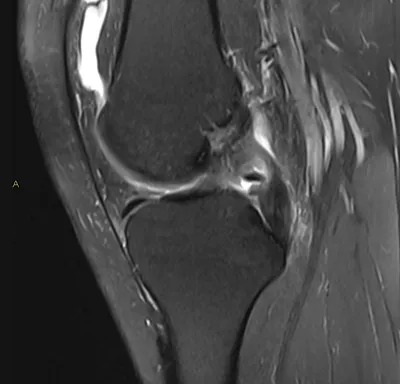

PCL Radiology Images

Browse 3 medical images tagged with pcl. This collection includes various imaging modalities for medical education and reference.

- This collection contains 3 radiology images related to pcl, including various imaging modalities such as X-rays, MRIs, CT scans, and ultrasound images commonly used in medical diagnosis and education.